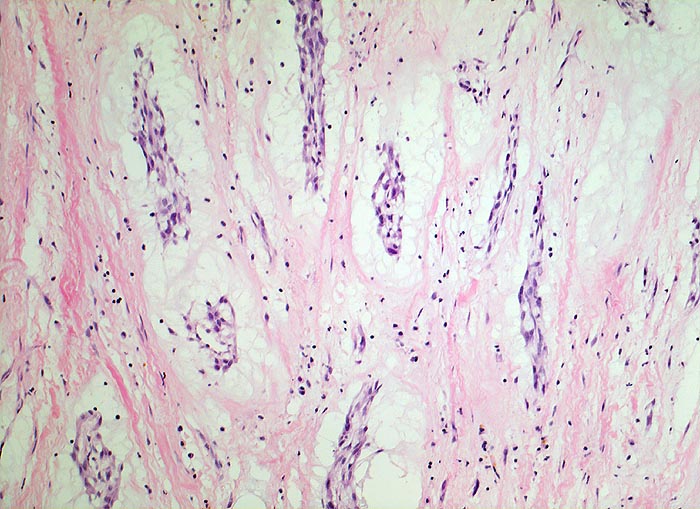

AP/ Vorhofmyxom

Vorhofmyxom